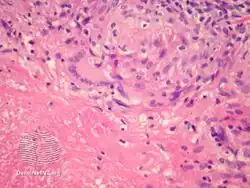

Histopathology

Lupus miliaris disseminatus faciei/pathology

Lupus miliaris disseminatus faciei/pathology-Dermatol_Sinica_2007%253B25(2)175-176-2.png.webp)